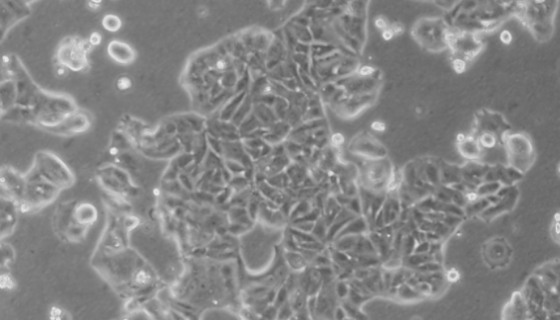

MDA-KB2人正常乳腺貼壁細(xì)胞系的特點(diǎn)與應(yīng)用!

MDA-KB2人正常乳腺貼壁細(xì)胞系是一種來源于人類乳腺癌的細(xì)...